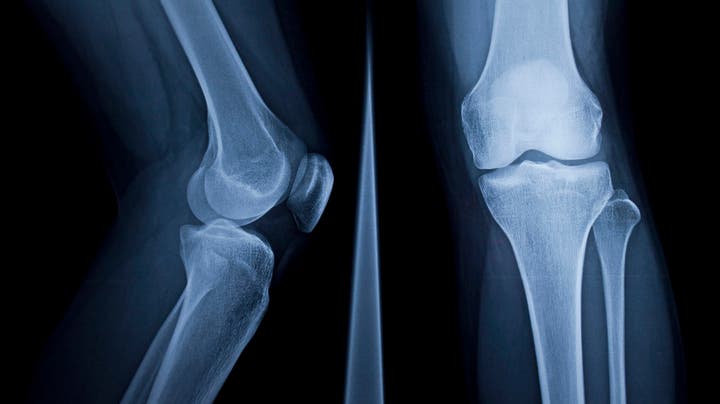

يمكن أن يكون تناول الفواكه الجافة طريقة رائعة لتعزيز صحة العظام بسبب محتواها الغني بالعناصر الغذائية، بما يشمل الكالسيوم والمغنيسيوم والبوتاسيوم والفيتامينات المختلفة.

وتقدم المكسرات والفواكه الجافة العشرة التالية فوائد صحية بشكل خاص لتقوية العظام: